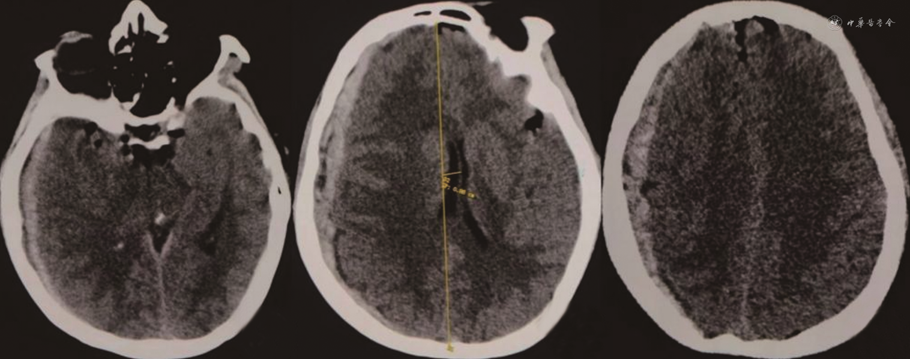

患者女性,55岁,慢性病程。患者自诉于2021年9月初无明显诱因偶发骶尾部疼痛不适感,起初程度轻微,不影响正常生活,后症状迁延,骶尾部疼痛发作频繁且程度加重,严重制约患者日常生活及工作。2021年10月4日入住甘肃省人民医院并于次日完善骶椎MRI检查,结果示骶椎椎管内见一类椭圆形长T1、长T2信号影,长径约2.5 cm(图1)。结合患者病史及影像学资料初步诊断为骶管囊肿。入院体检:骶尾部压痛,其余各项体检结果均未见明显异常。术前完善相关检查,排除手术禁忌证,于2021年10月10日全身麻醉下行后正中入路显微镜下骶管囊肿切除术与脊神经粘连松解术,于麻醉苏醒后返回我科神经重症监护室,予以重症监护,患者嗜睡,轻度恶心,无呕吐,约10 min后患者突发呼之不应,右侧瞳孔散大,直径约5.0 mm,直接及间接对光反射消失,左侧瞳孔直径约2.5 mm,直接及间接光反应灵敏,急予250 ml甘露醇快速静脉点滴并急诊完善头部CT,CT影像学检查结果提示:右侧额顶颞枕部硬膜下血肿,中线由右向左偏移,环池欠清,脑干受压明显(图2)。患者病情危重,遂急在全身麻醉下行右额颞开颅硬膜下血肿清除+骨瓣还纳术,术中未见颅骨骨折、颅内原发性损伤病灶。术后6 h后患者意识状态逐渐恢复,复查头颅CT提示硬膜下血肿清除干净,中线居中,颅内无再出血及梗死表现(图3)。术后采取头高足低位,予以控制颅内压、补液及营养支持等对症治疗后好转离院。定期随访观察并于出院7个月后我院复查头颅MRI提示:右侧额顶颞枕部颅板下片状混杂信号,等T1、长T2信号,脑沟、裂、池未见受压影像,中线结构居中(图4)。患者恢复良好,无明显后遗症。